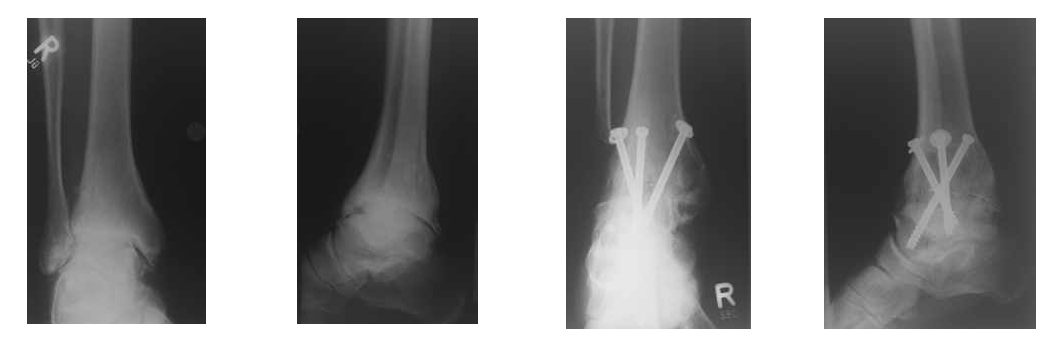

Osteochondrosis dissecans tali

Die Osteochondrosis dissecans der Talusschulter am oberen Sprunggelenk (Durchblutungsstörung des Sprungbeines) kann bei Beschwerden im Erwachsenenalter durch Anbohrung des Knochens behandelt werden, um die Durchblutung zu verbessern. Ist der Knorpel-Knochen-Komplex bereits eingebrochen, kann eine Knorpel-Knochentransplantation (OATS oder Mosaikplastik) durchgeführt werden. Hierzu werden ein oder mehrere Knorpel-Knochenzylinder aus dem Kniegelenk entnommen, welche dann im Sprungbein (Talus) eingesetzt werden und den zerstörten Gelenkanteil ersetzen. Hierzu ist es oft nötig, dass der Innenknöchel durchtrennt werden muss, um den Defekt im Sprungbein behandeln zu können. Der Innenknöchel wird anschließend wieder mit einer Schraube und einem Draht fixiert. Eine mehrere Woche dauernde Entlastung zur Einheilung des Knorpel-Knochenzylinders und Innenknöchelheilung ist hierfür nötig.